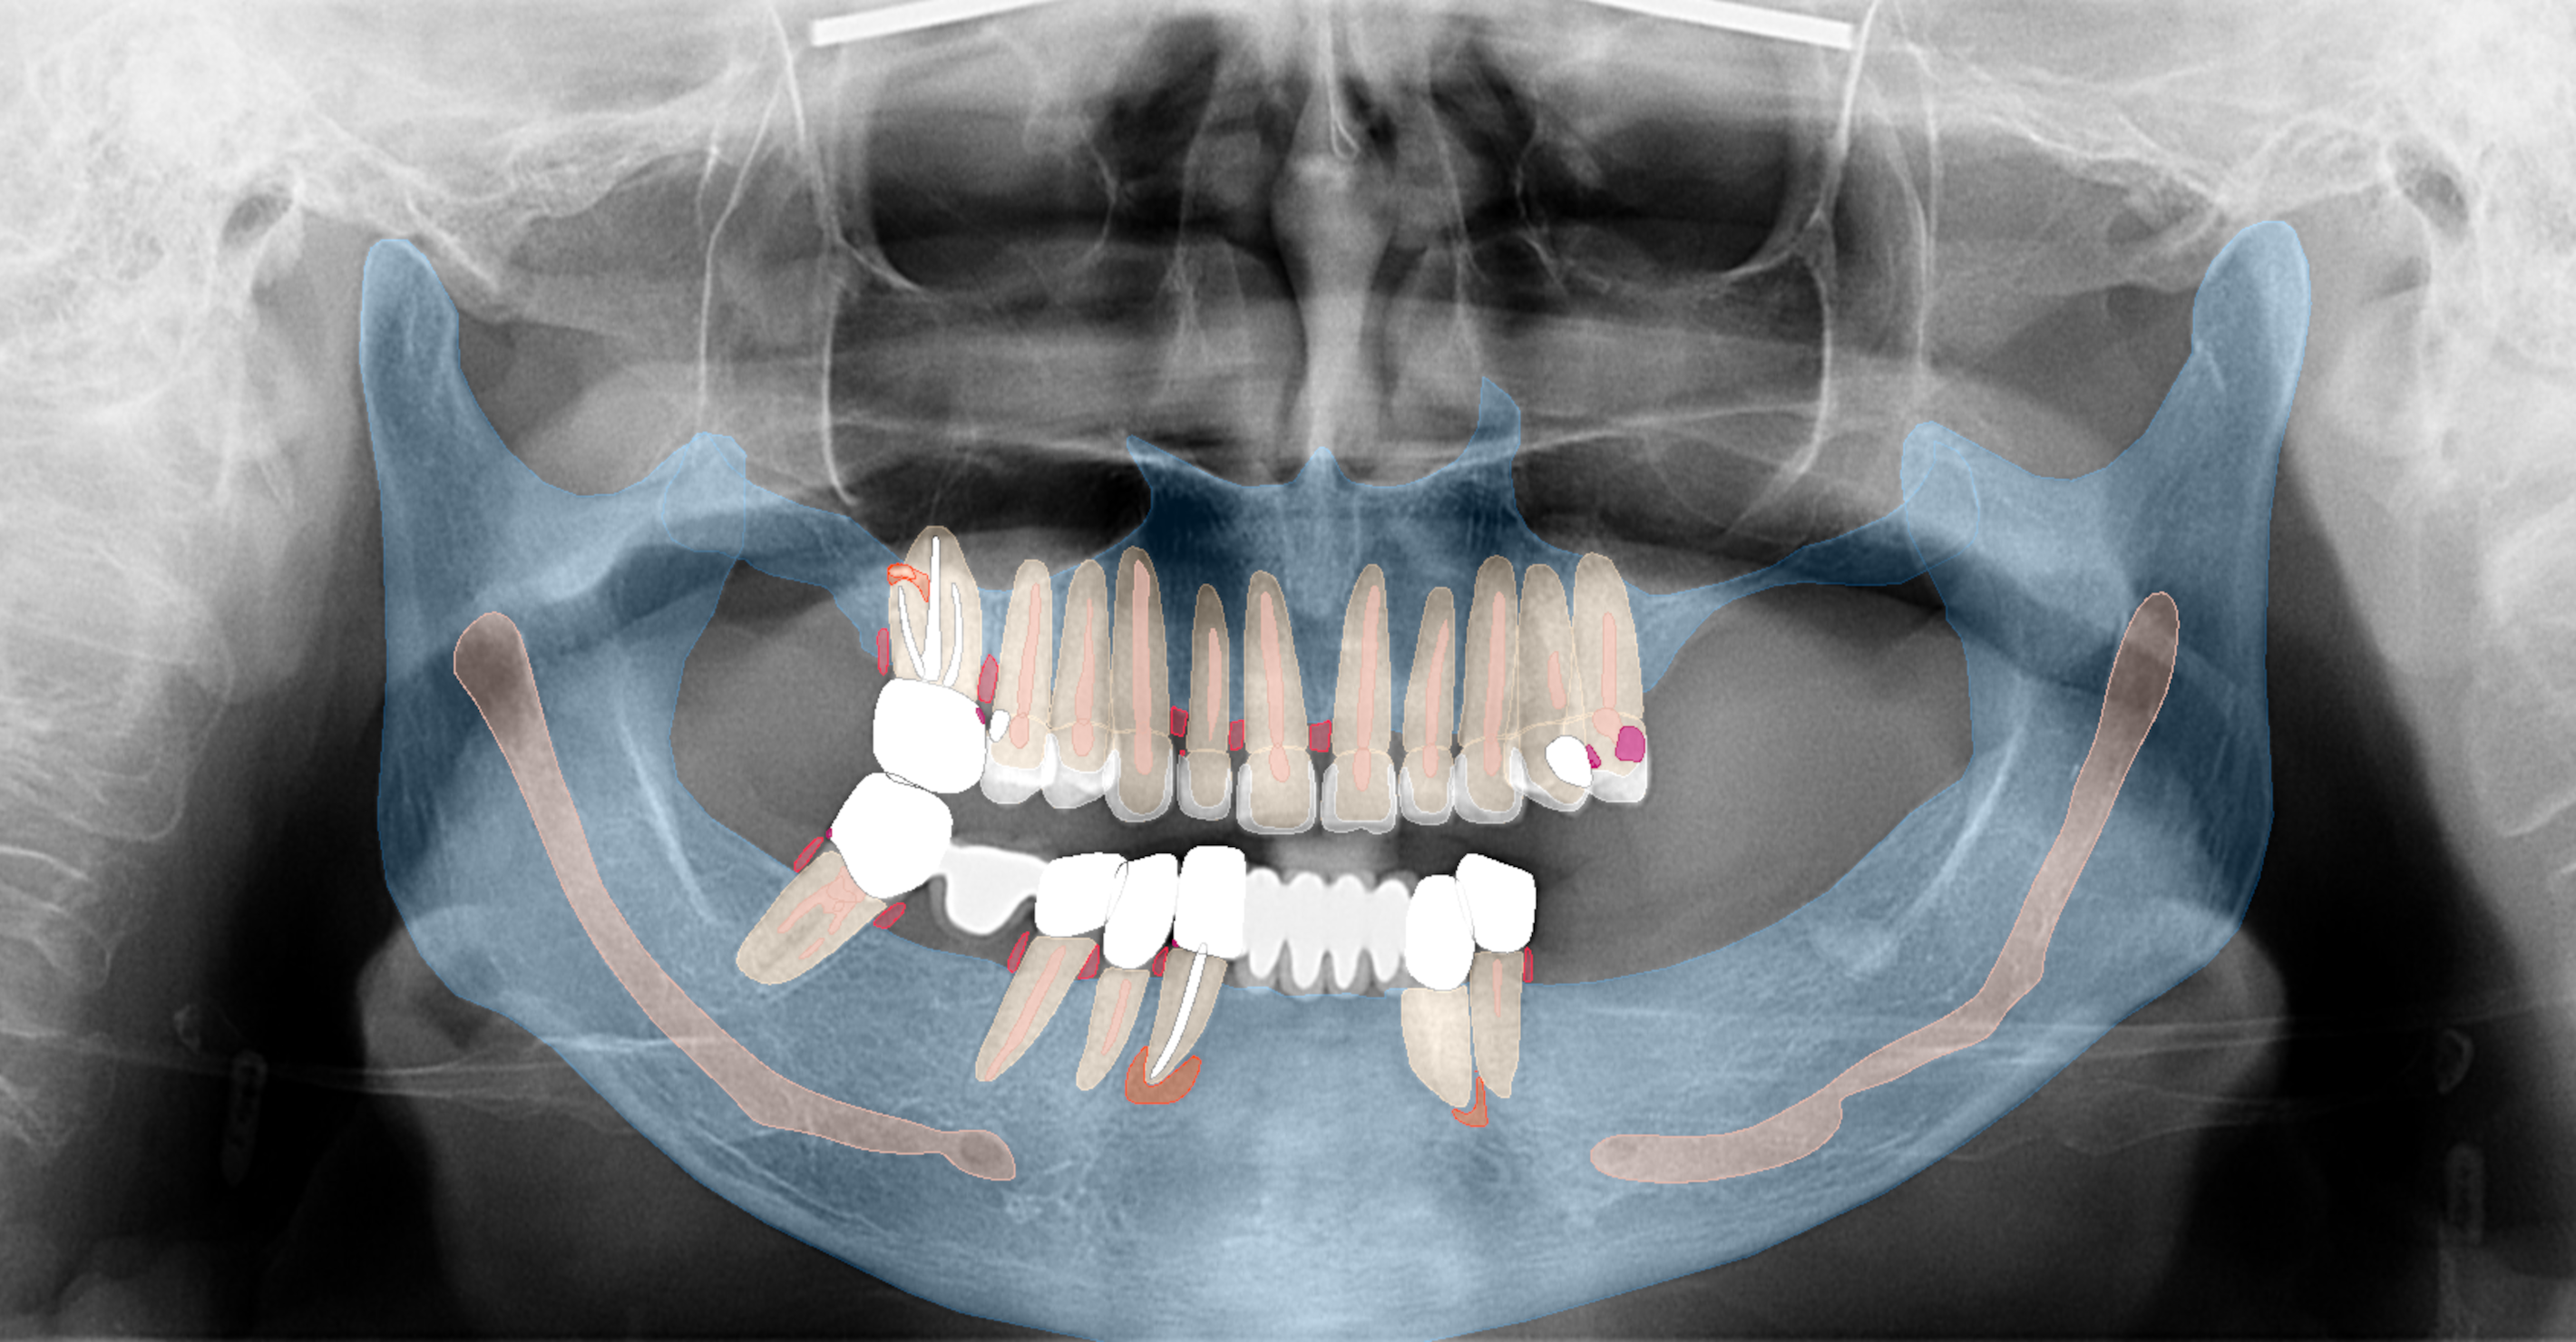

Fig. b: Pre-op panoramic radiograph and the findings.

Intra-oral examination revealed compromised mandibular dentition, an old fixed prothesis, missing posterior teeth on the left side, periodontal involvement and gingival inflammation. A panoramic radiograph was obtained, and the findings were reported to the patient (Figs. 1a & b; 2a & b). Both mandibular canines had visible periapical radiolucencies. A CBCT scan was performed for a more detailed assessment of the alveolar bone anatomy (Figs. 3a & b). Temporomandibular joint examination revealed no indication of dysfunction (crepitus, clicking or pain).